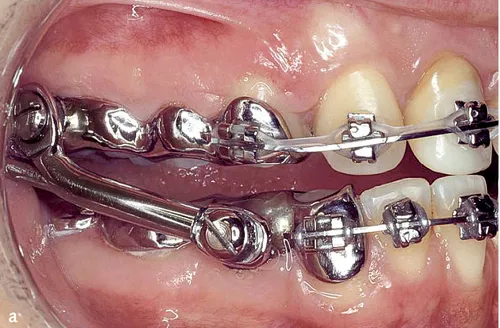

Abb. 2a bis c Beispiele von drei festsitzenden FKO-Geräten: a) Herbst-Apparatur, b) Jasper Jumper und c) Forsus Fatigue Resistance Device.